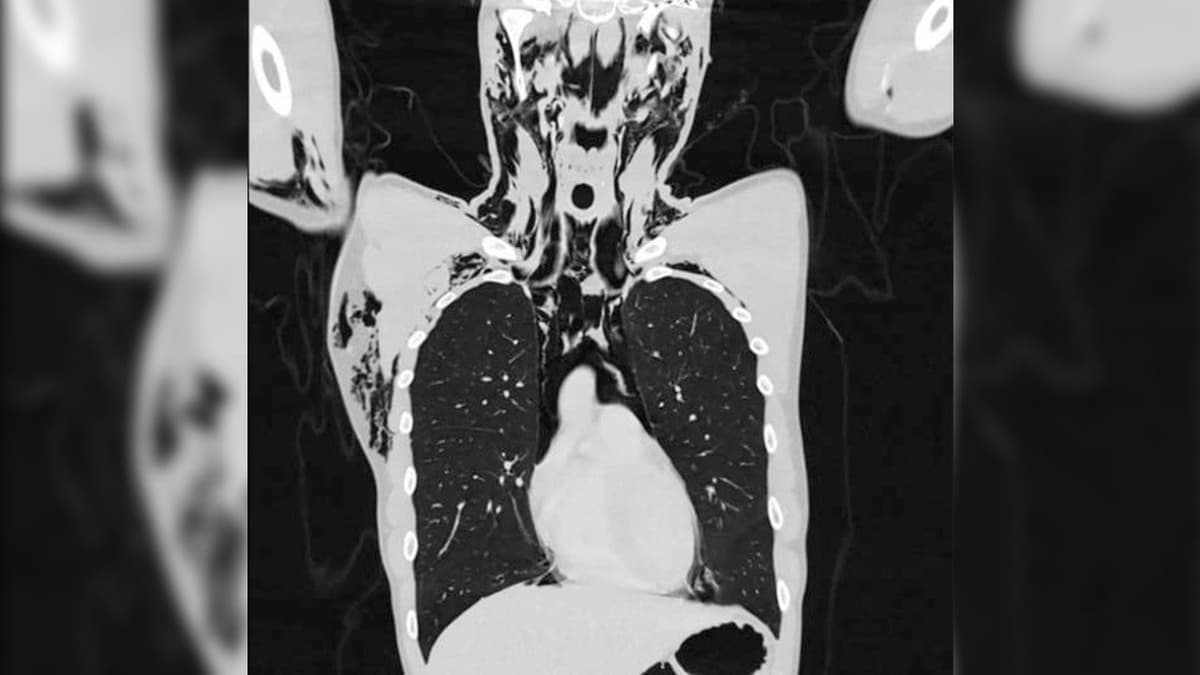

El sujeto acudió al hospital donde los médicos realizaron radiografías. Los resultados arrojaron que el joven sufría un padecimiento descrito como la presencia de aire que escapa de los pulmones y queda atrapado en la caja torácica.

Y eshombre en Suiza se masturbó tan agresivamente que estuvo cerca de morir al sufrir un fuerte dolor en el pecho. que el ‘neumomediastino’ espontáneo se define como aire libre dentro del mediastino. Se asocia con ejercicio, drogas, asma, vómitos, entre otras cosas. Es más frecuente en hombres jóvenes.

“Un hombre joven de 20 años (175 cm, 60 kg) fue asignado a nuestro servicio de urgencias con disnea intensa y dolor torácico. Informó un inicio repentino de dolor agudo en el pecho seguido de dificultad para respirar mientras estaba acostado en la cama masturbándose”, fue el reporte.